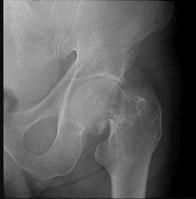

问题 图示骨折后,下列哪一体征不可能出现 ( )

选项 A、患肢略长于健肢 B、Shoemaker线相交于脐下 C、Bryant三角底边缩短 D、患肢外展、外旋、缩短畸形 E、髋部叩击痛

答案 A